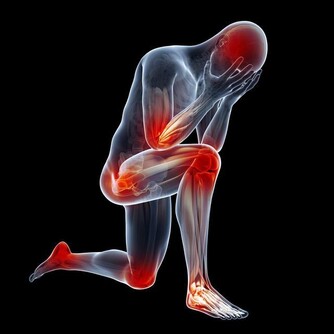

防治痛風的原則包括以下幾個方面:

1、 合理控制飲食:此項是痛風防治的基礎,即所有的防治措施都應該在此基礎上進行,才能取得好的效果.包括患者總熱能的維持以醣類為主,適當地限制高蛋白,高熱能食物的攝入,控制脂肪的攝人,堅持低嘌呤飲食,戒除菸酒.提倡和鼓勵患者多飲水,保持每天尿量在2000毫升以上,可促進尿酸排泄。

2、 科學的生活方式:按時起居,勞逸適度,避免過度疲勞,緊張與激動.適應季節氣候變化,避免濕冷與感冒.鞋襪要舒適,避免關節損傷.在避免過度勞累與損傷的前提下,適當參加體育活動,如打太極拳,散步,慢跑, 舞蹈,體操等,以保持體形,增強體質。

3、 有效的藥物治療:在醫生的指導下,堅持服藥以控制痛風的發作或反復發作,維持血尿酸在正常範圍內,防止損害腎臟與關節。

4、 定期的健康檢查

痛風與糖尿病一樣是終生疾病。關鍵是自己控制飲食,多食含“嘌呤”低的鹼性食物,如瓜果、蔬菜,少食肉、魚等酸性食物,做到飲食清淡,低脂低糖,多飲水,以利體內尿酸排泄。